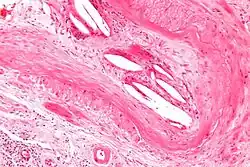

| Micrograph showing a cholesterol embolus in a medium sized artery of the kidney. Kidney biopsy. H&E stain. | |

The microscopic examination of tissue (histology) gives the definitive diagnosis. The diagnostic histopathologic finding is intravascular cholesterol crystals, which are seen as cholesterol clefts in routinely processed tissue (embedded in paraffin wax).[7] The cholesterol crystals may be associated with macrophages, including giant cells, and eosinophils.

The sensitivity of small core biopsies is modest, due to sampling error, as the process is often patchy. Affected organs show the characteristic histologic changes in 50-75% of the clinically diagnosed cases.[3][5] Non-specific tissue findings suggestive of a cholesterol embolization include ischemic changes, necrosis and unstable-appearing complex atherosclerotic plaques (that are cholesterol-laden and have a thin fibrous cap). While biopsy findings may not be diagnostic, they have significant value, as they help exclude alternate diagnoses, e.g. vasculitis, that often cannot be made confidently based on clinical criteria.